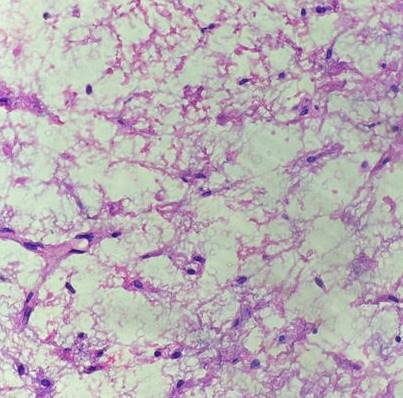

Histopathological examination showed an unencapsulated tumor mass showing spindle and stellate-shaped cells in loose connective tissue stroma with delicate collagen fibers and rich vascularization, concluding an odontogenic myxoma (OM). (Figure 6)

Figure 6. Microscopic appearance of the lesion showing stellate and spindle-shaped cells in a myxoid matrix (original magnification × 40).